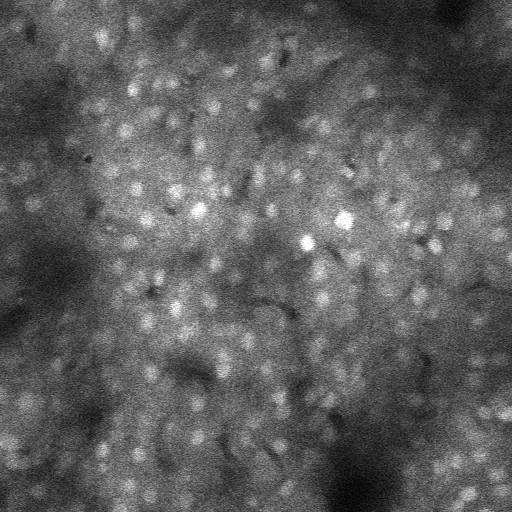

The following figure shows an example of calcium brain neuron image and the detected neurons. The blue circles are detected neurons (or, more precisely, the "Regions of Interest -- ROIs"). The red circle inidiates the signal analyis of the neuron that is being shown on the interface.